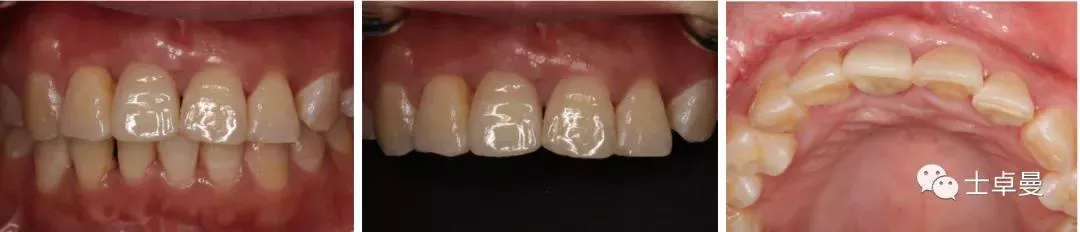

二期术前口内照及CBCT

种植体植入后6个月

·      安装临时修复体;

·      临时修复体安装2个月后调整穿龈形态及邻面接触点位置;

·      临时修复体安装6个月后,牙龈形态良好,唇侧软组织稳定;

·      个性化取模;

·      最终修复;

·      最终修复CBCT。

本病例利用颏部的自体骨块修复前牙区垂直骨缺损,以确保能在理想的位点进行种植体的植入,从而获得良好的美学及功能效果。